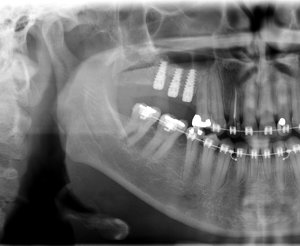

Enxerto de seio maxilar